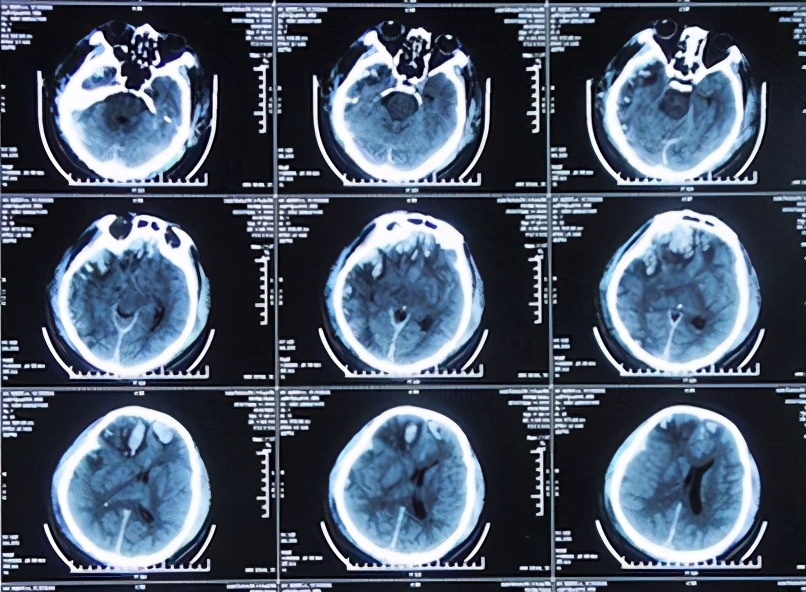

患者于2013年9月17日凌晨因车祸致头部外伤、昏迷,急诊于山东省聊城市某医院就诊,头CT检查发现双额及右颞叶多发脑挫裂伤并右侧脑室受压、中线左移(图-1),当天进行了右侧额颞叶脑挫裂伤血肿清除并去骨瓣减压术,术后头CT:去骨瓣减压术后状态(图-2)。

图-1:2013年9月17日术前头CT

图-2:2013年9月17日术后头CT